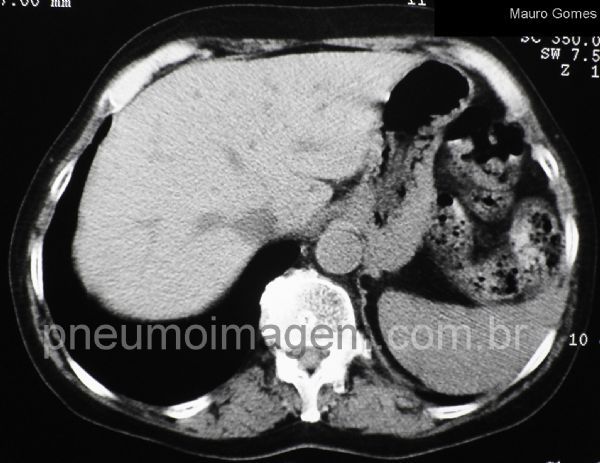

A amiodarona também se acumula no fígado e o órgão pode aparecer mais denso. A atenuação hepática aumentada pode ocorrer nos indivíduos tratados pela droga mesmo na ausência de toxicidade medicamentosa.

Amiodarone also accumulates in the liver and the organ may appear thicker. The increased hepatic attenuation may occur in subjects receiving the drug even in the absence of drug toxicity.